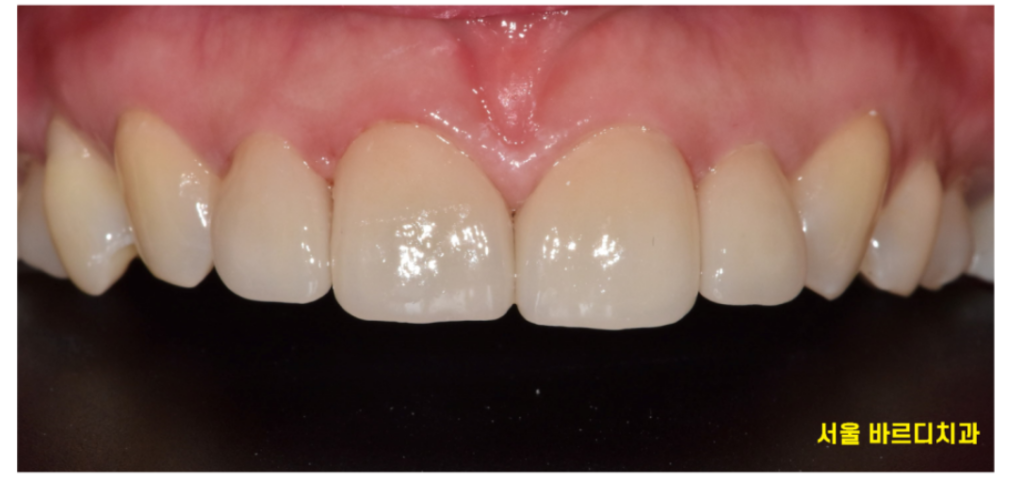

어떤게 라미네이트일까요~??

감쪽같죠~??

보철이라 해서 티가 나면 안됩니다.

어떤것이 라미네이트 치아인지 감쪽같게

만들어 드리는게 기술력이죠!!!

작은 치아로 고민하시던 환자분은

앞니 4개 치아 사이즈를 재분배하여

컴플렉스 극복시켜 드렸습니다.